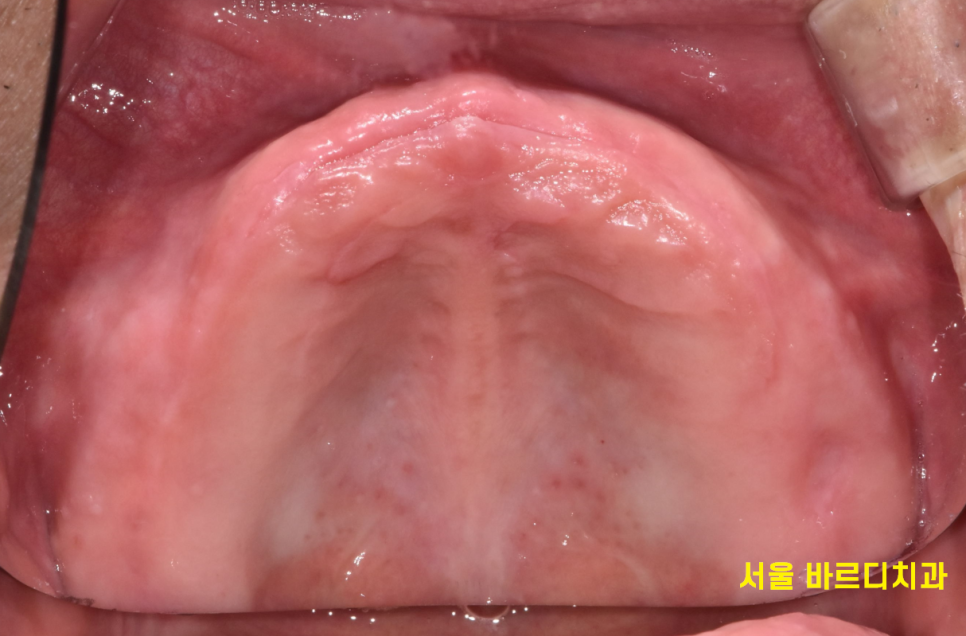

이런 경우에는 윗니는 치아가 1개도 없으니

보험 임플란트는 적용이 안될 것이고

아래 치아는 앞니 4개가 남아있으니

국가 지원 임플란트 혜택을 보실 수가 있겠습니다~